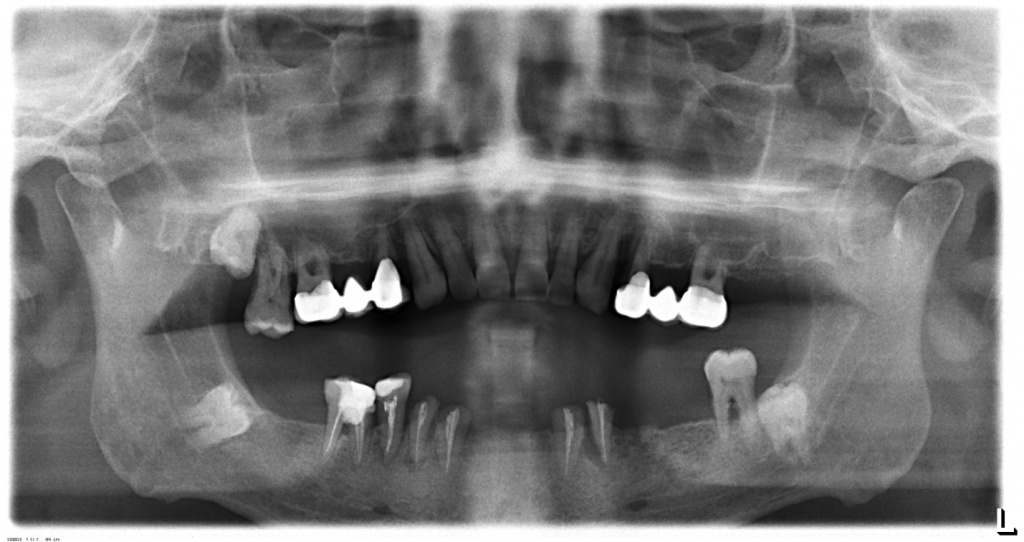

Ортопантомограммы пациентов до и сразу после имплантации. В 1-ом случае имплантат в позиции 36 и 27 , а на 2-ом снимке часть имплантатов установлены немедленно после удаления зубов.

CASE №1

Планируется установка имплантата в позиции 17.